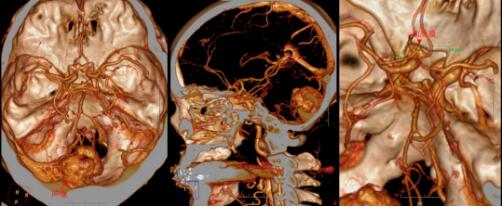

血管母细胞瘤是一类血供极为丰富的肿瘤,实质性血管母细胞瘤尤甚。术前完善的CTA检查,了解肿瘤血供相当必要。进一步的头颅CTA检查提示肿瘤的血供极为丰富,存在有多处供血动脉。然而,屋漏偏遭连夜雨,CTA检查还发现患者的前交通动脉上鼓了个小泡——也就是动脉瘤,也就是常常被脑外科大夫们形容为“不定时炸弹”的颅内病变,病死率相当高!

▲术前CTA:肿瘤血供丰富,多支供血动脉存在

▲术前CTA:前交通动脉瘤存在,大小3.2mm×3.4mm

于是,欧阳辉主任再次组织医护团队进行了讨论,患者颅内动脉瘤尚未破裂,并且动脉瘤大小约为3.5mm,手术破裂的风险相对较小。手术的首要目的在于切除后颅窝小脑肿瘤,解除占位效应及脑疝威胁,缓解脑积水。考虑到肿瘤血供极为丰富,存在多处供血动脉,应当配备充足血液,手术切除前应行肿瘤供血动脉的部分栓塞,以减少术中出血,提高手术成功率。

神经血管介入科主任王培明先行肿瘤部分供血血管栓塞后,欧阳辉主任带领团队对患者的左侧小脑肿瘤进行了手术切除。

术中证实了团队的术前推断,肿瘤为较大的实质-囊性血管母细胞瘤。手术过程虽惊险不断,但团队“艺高人胆大”,依靠过硬的手术技术,顺利完成手术。